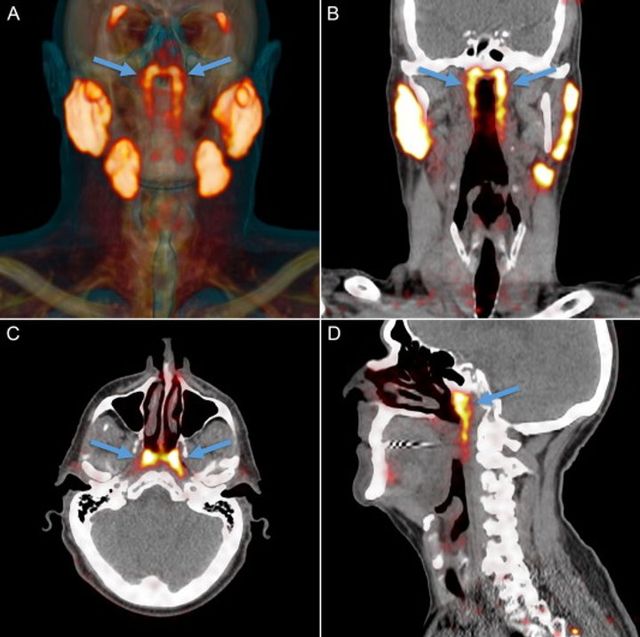

Науковці з Нідерландів обстежували пацієнтів і наткнулися на несподівану знахідку - всередині людської голови виявили невідомий раніше набір слинних залоз.

Всього донині вважалося, що в людини є три набори слинних залоз. Нововиявлена пара розміщена майже у центрі голови, між носом і над піднебінням.

Перевіривши 100 пацієнтів, чоловіків та жінок, науковці знайшли такий самий орган у всіх. Проте, для того, аби робити остаточні висновки, доведеться провести масштабніше дослідження.